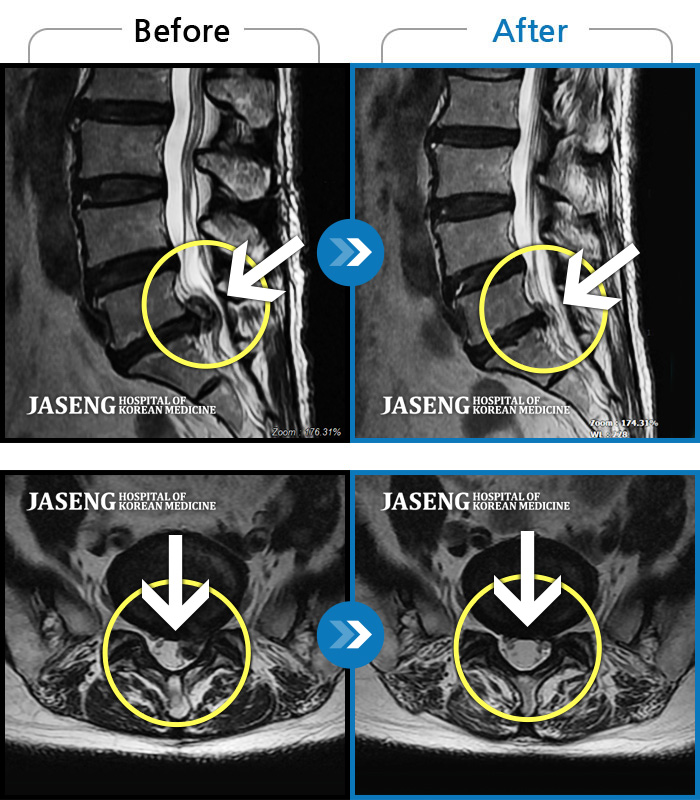

일상생활을 못할 정도로 안좋아서 수술권유 받은 상태에서 마지막 지푸라기라도 잡는 심정으로 가게 되었는데.

기적처럼 수술없이 통증이 좋아졌습니다.

원장님 처음 설명 해주신대로 치료받으니 빨리 좋아져서 덕분에 일도 할 수 있는 상태가 되었네요.